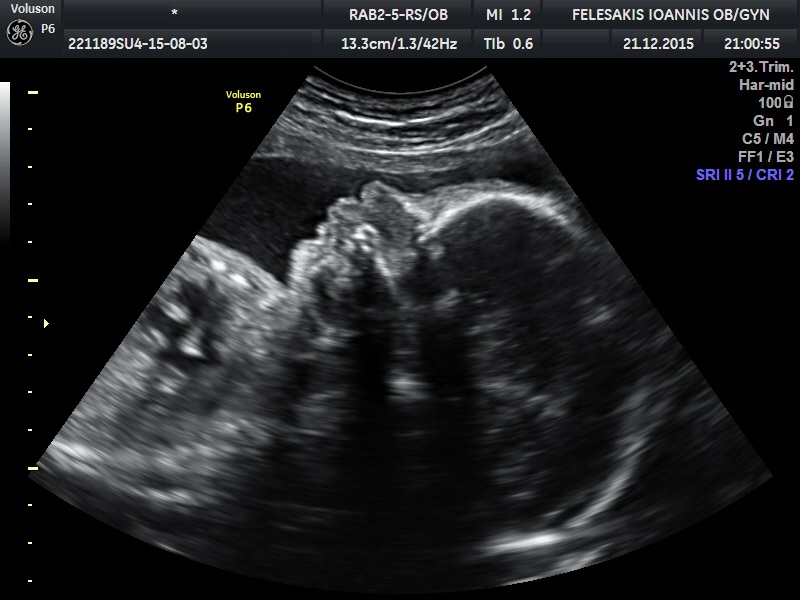

Η υπερηχογραφική αυτή εξέταση επιτελείται από την 20η εώς την 24η εβδομάδα κυήσεως από ιατρούς ειδικά εκπαιδευμένους οι οποίοι κατόπιν εξετάσεων έχουν λάβει την πιστοποίηση για τη διετέλεση υπερήχων β επιπέδου. Ελέγχεται η σωματική ανάπτυξη και την ανατομία του εμβρύου τη δεδομένη στιγμή. Εξετάζονται αναλυτικά ο εγκέφαλος, το πρόσωπο, ο θώρακας, οι πνεύμονες, η καρδιά, η κοιλιά, οι νεφροί και η ουροδόχος κύστη, η σπονδυλική στήλη και τα άκρα του εμβρύου.Προσδιορίζουμε τη θέση του πλακούντα, τον όγκο του αμνιακού υγρού και διαπιστώνουμε την ύπαρξη δεικτών (softmarkers) οι οποίοι σχετίζονται με χρωμοσωμικές ανωμαλίες.